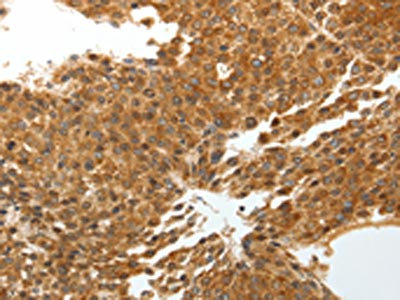

The image on the left is immunohistochemistry of paraffin-embedded Human liver cancer tissue using CSB-PA976408(TNXB Antibody) at dilution 1/40, on the right is treated with synthetic peptide. (Original magnification: ×200)